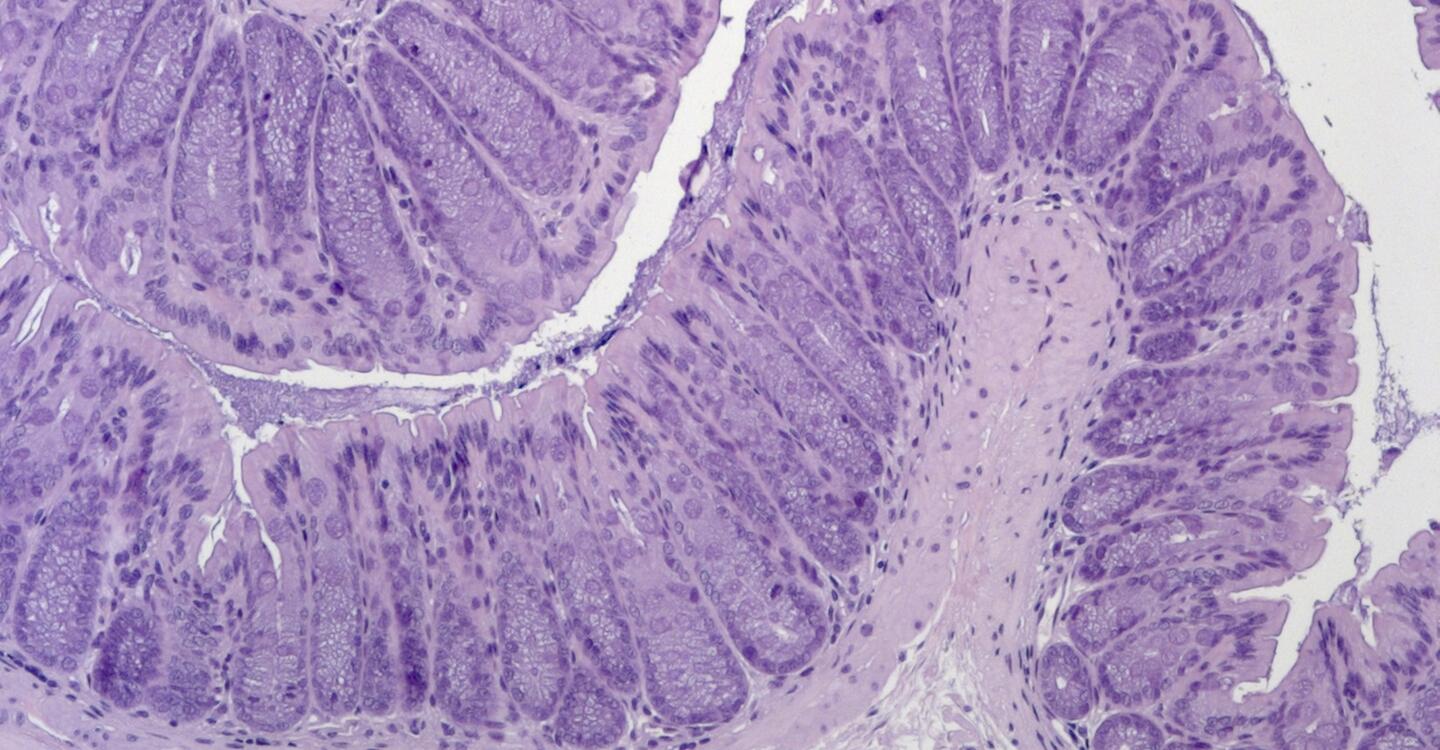

© Anja Kühl, Charité

Das Bild zeigt Darmgewebe aus einem Mausmodell für die erworbene generalisierte Lipodystrophie. Das Gewebe blieb auch nach der Behandlung mit einer Chemikalie, die normalerweise eine Darmentzündung auslöst, intakt.